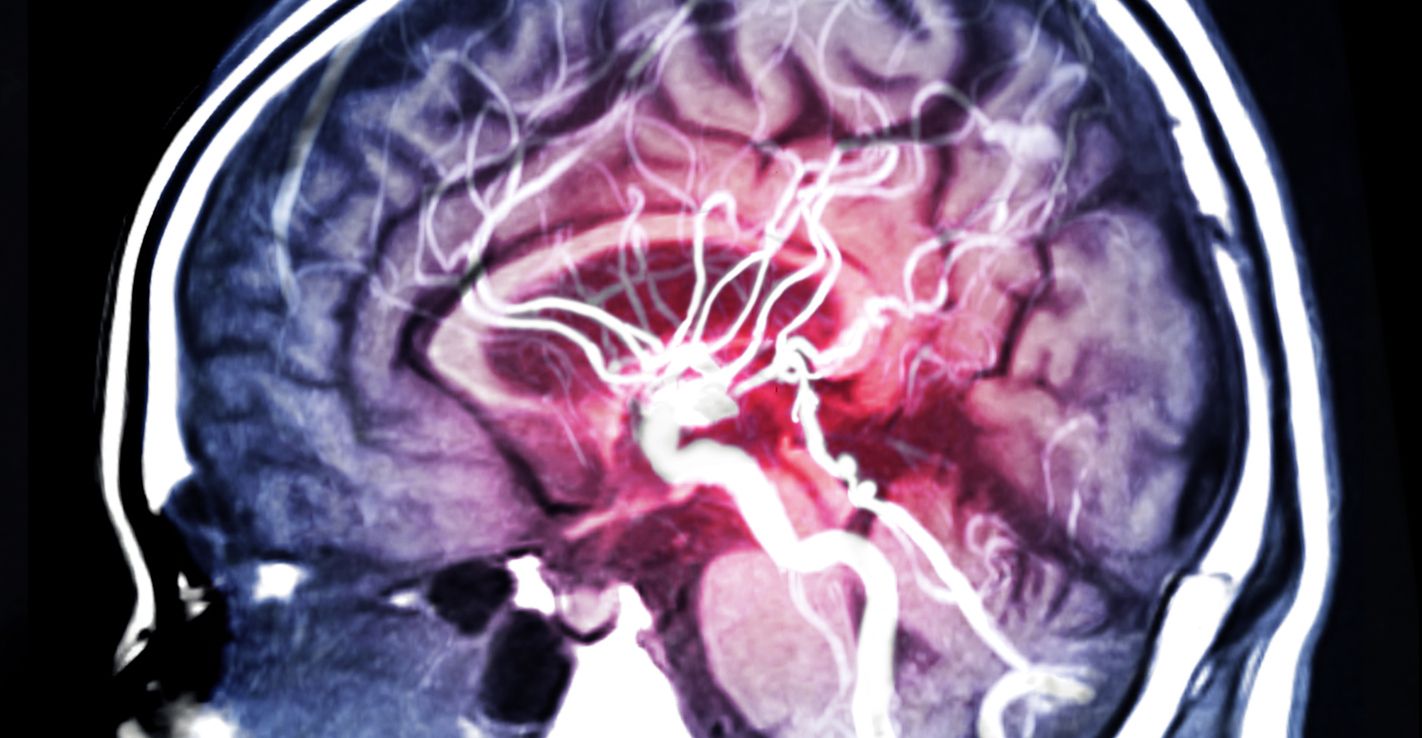

Forscher vom deutschen Universitätsklinikum Freiburg haben nun eine interessante Entdeckung gemacht. Laut ihrer neuen Studie hinterlässt Corona bei jedem, der daran erkrankt ist, eine immunologische "Narbe" im Gehirn.

Die Forscher untersuchten die Gehirne von 15 Personen, die an COVID-19 erkrankt, vollständig genesen und zu einem späteren Zeitpunkt an einer anderen Ursache verstorben waren. In den Gehirnen dieser Menschen fanden die Mediziner zahlreiche sogenannte Mikroglia-Knötchen.

Diese Ansammlungen von Immunzellen weisen auf eine chronische Immunaktivierung hin –  ähnlich einer Narbe, die nicht vollständig ausheilt. "Die Mikroglia-Knötchen könnten eine zentrale Rolle bei den neurologischen Veränderungen spielen, die bei einigen Genesenen beobachtet werden", erklärt Dr. Marius Schwabenland, Erstautor der Studie, Assistenzarzt am Institut für Neuropathologie des Universitätsklinikums Freiburg.

Bei Personen, die nie mit Corona infiziert waren, wurden diese Mikroglia-Knötchen nicht gefunden.